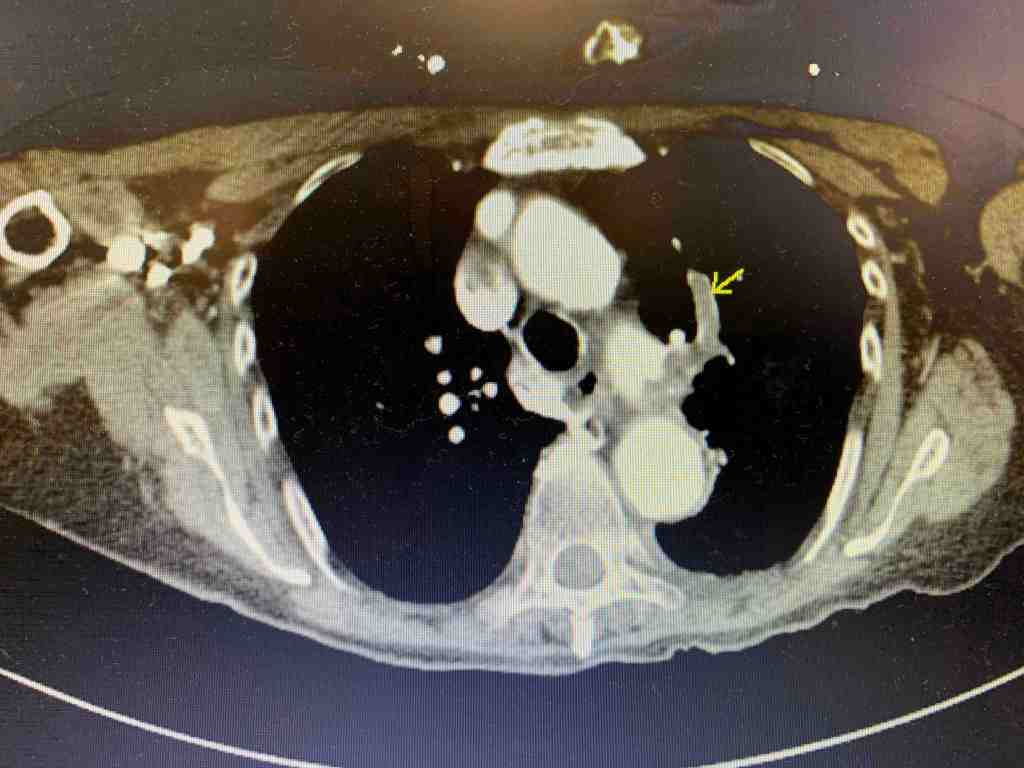

Given the above bedside ultrasound, there was concern for PE as the cause of the patient’s hypoxia. CTA was obtained and showed bilateral segmental PE’s.

The patient was started on anticoagulation and admitted. Her blood pressure remained stable but she continued to require 6L of O2 by NC and her troponin continued to rise. Cardiology based echo showed: